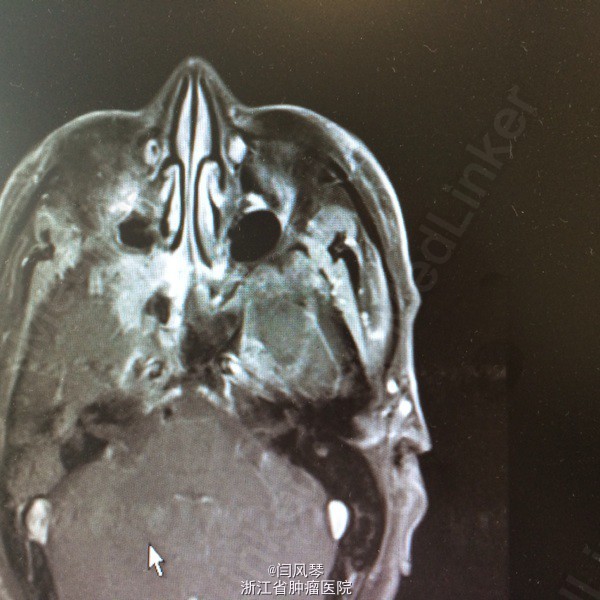

患者男,58岁,鼻咽癌放疗近2年,因鼻咽部复发于2015.6.12-2015.8.25于当地医院行TP方案化疗4周期,现化疗后1月余,诉右耳听力下降,右侧口角周围皮肤麻木感,为进一步诊治就诊于我院,门诊拟“鼻咽恶性肿瘤复发”收治。

一般可,生命体征平稳,鼻咽右侧壁及顶壁见新生物,双颈部未及明显肿大淋巴结。

诊断:鼻咽恶性肿瘤复发。治疗:复发灶局部放疗

讨论:患者鼻咽部放疗后复发,行4周期化疗后,肿瘤残留较明显,有局部放疗指征,但患者首程放疗后近两年,时间较短,再程放疗易引起鼻咽部溃疡大出血、放射性脑病、放射性神经损伤灯较严重的并发症,需积极预防及治疗